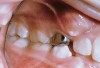

An 11½-year-old female was referred for treatment of her severe crowding, with her dentist expecting a return visit for extractions. The patient’s dentition was severely crowded (Figure 7), with completely blocked-out canines. Her buccal occlusion (Figure 8) was a good Class I with the primary first and second molars still present. Will this patient require extraction to decrowd the blocked-out cuspids, or is this a nonextraction case? The clinician cannot make a decision with this information only. Without further knowledge of the face and smile, the immediate answer is “yes.” This patient was selected for an illustrative case presentation for the following reasons: 1) the long-term changes of the face were an important factor in evolving the orthodontic treatment plan; 2) she represents an excellent illustration of how knowledge of the differential hard- and soft-tissue changes that occur during growth and maturation guides the treatment plan; 3) to demonstrate how the principles of soft-tissue growth can be used to the maximum advantage; and 4) to emphasize how traditional cephalometric hard-tissue standards for treatment planning have a less significant place in the decision-making process.

Figure 7  This patient had severe crowding with completely blocked-out canines. Premolar extraction appears to be inevitable.

Figure 7

Figure 8  The occlusion was Class I, and this image clearly shows the spacing issues present.

Figure 8